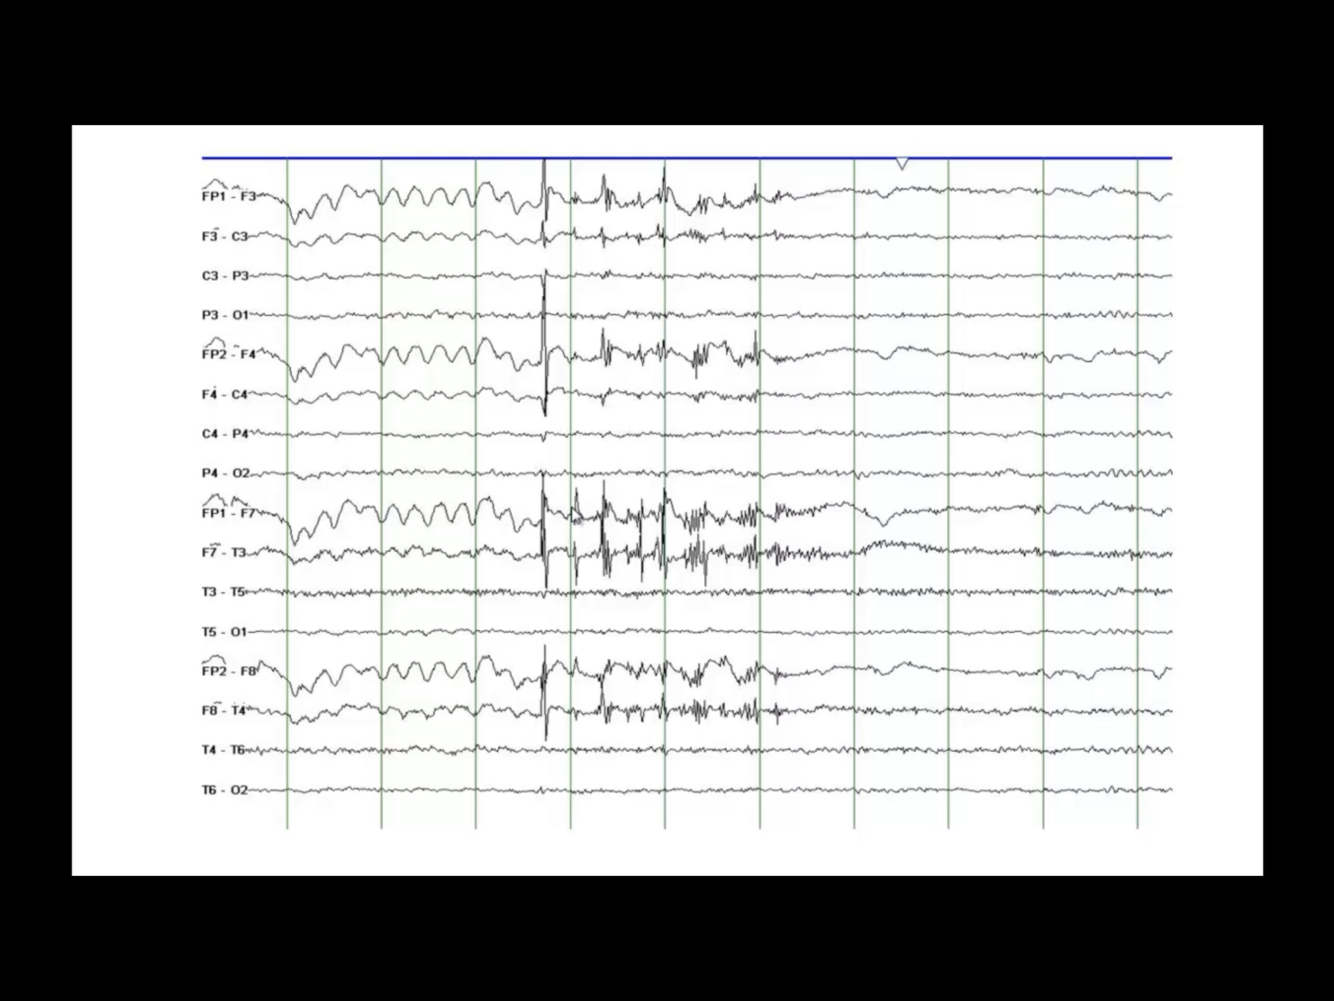

Wicket Spikes

• 6-11 Hz

• Temporal

• Unilateral/bilateral

• Medium-high amplitude

• Older adults

• Drowsy/light sleep

• Arciform/wicket-like appearance